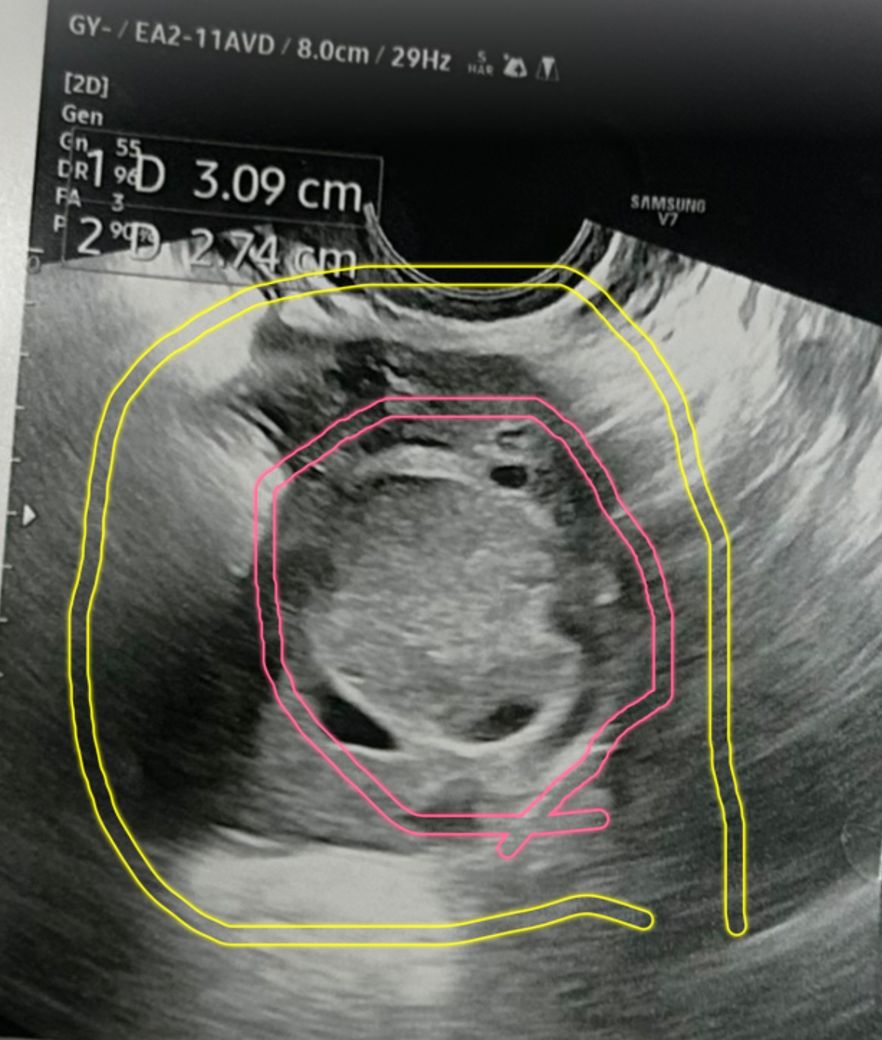

왼쪽난소는 절제했고 오른쪽 난소에 혹이 보이는데 cyst 는 아니라는데 뭘까요?

노란색 원은 난소인데 핑크색 안이 혹이래요

초음파 사진이에요